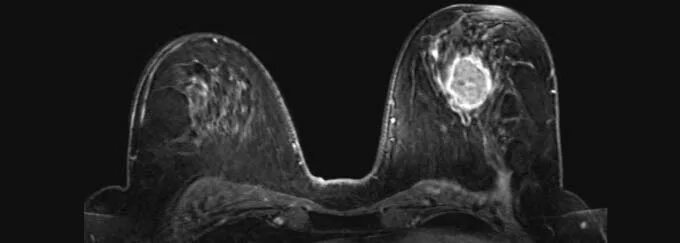

Мрт молочных желез